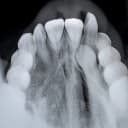

PA (عکس پریاپیکال)